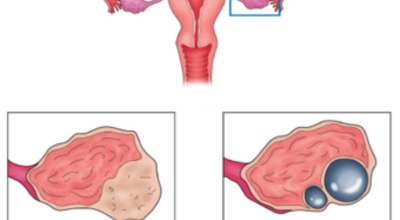

난소낭종이란 난소에 발생되는 물혹이지요. 안에는 그냥 수액이나 장액이지만, 혈액일 수도 있으며, 지방이나 농양일 수도 있어요. 이 난소낭종은 없어졌다 생겼다 하는 기능성 낭종과 점점 커지는 악성 낭종으로 나뉘는데요. 주로 악성 낭종이 문제일 것이라고 생각하지만 기능성 낭종도 커지면 터지면서 사람을 응급실로 실려가게 만들어요.

먹는 피임약을 복용함으로서 치료를 할 수도 있는데, 약을 복용함에도 불구하고 계속해서 낭종이 관찰된다면 수술이 고려되기도 합니다. 난소낭종이 파열되는 원인은 낭종(혹)이 꼬이거나 복강 내에서 파열되기 때문인데 복강 내 출혈과 급성 복통을 유발할 수 있어요.